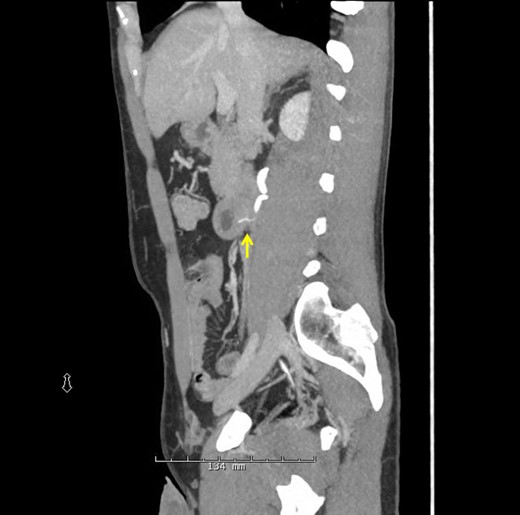

Sagittal CT scan again demonstrating the FB through the posterior wall of the duodenum onto the anterior surface of the ureter.

Urology performed a right retrograde pyelogram demonstrating a point of obstruction in the proximal ureter with no contrast extravasation. A guide wire and stent were passed through the obstruction into the hydronephrotic right kidney without difficulty. Following successful stent insertion, fluoroscopy was used to confirm the location of the FB at the junction of the second and third portion of the duodenum. A full Kocher maneuver was performed and the duodenum and ureter were separated. A small, linear, FB was identified projecting from the posterior third portion of the duodenum into the ureter (Fig. 3) and extracted without injury (Fig. 4). The patient's original abdominal pain resolved after the surgery. He was able to tolerate a diet and be discharged on postoperative day 4.